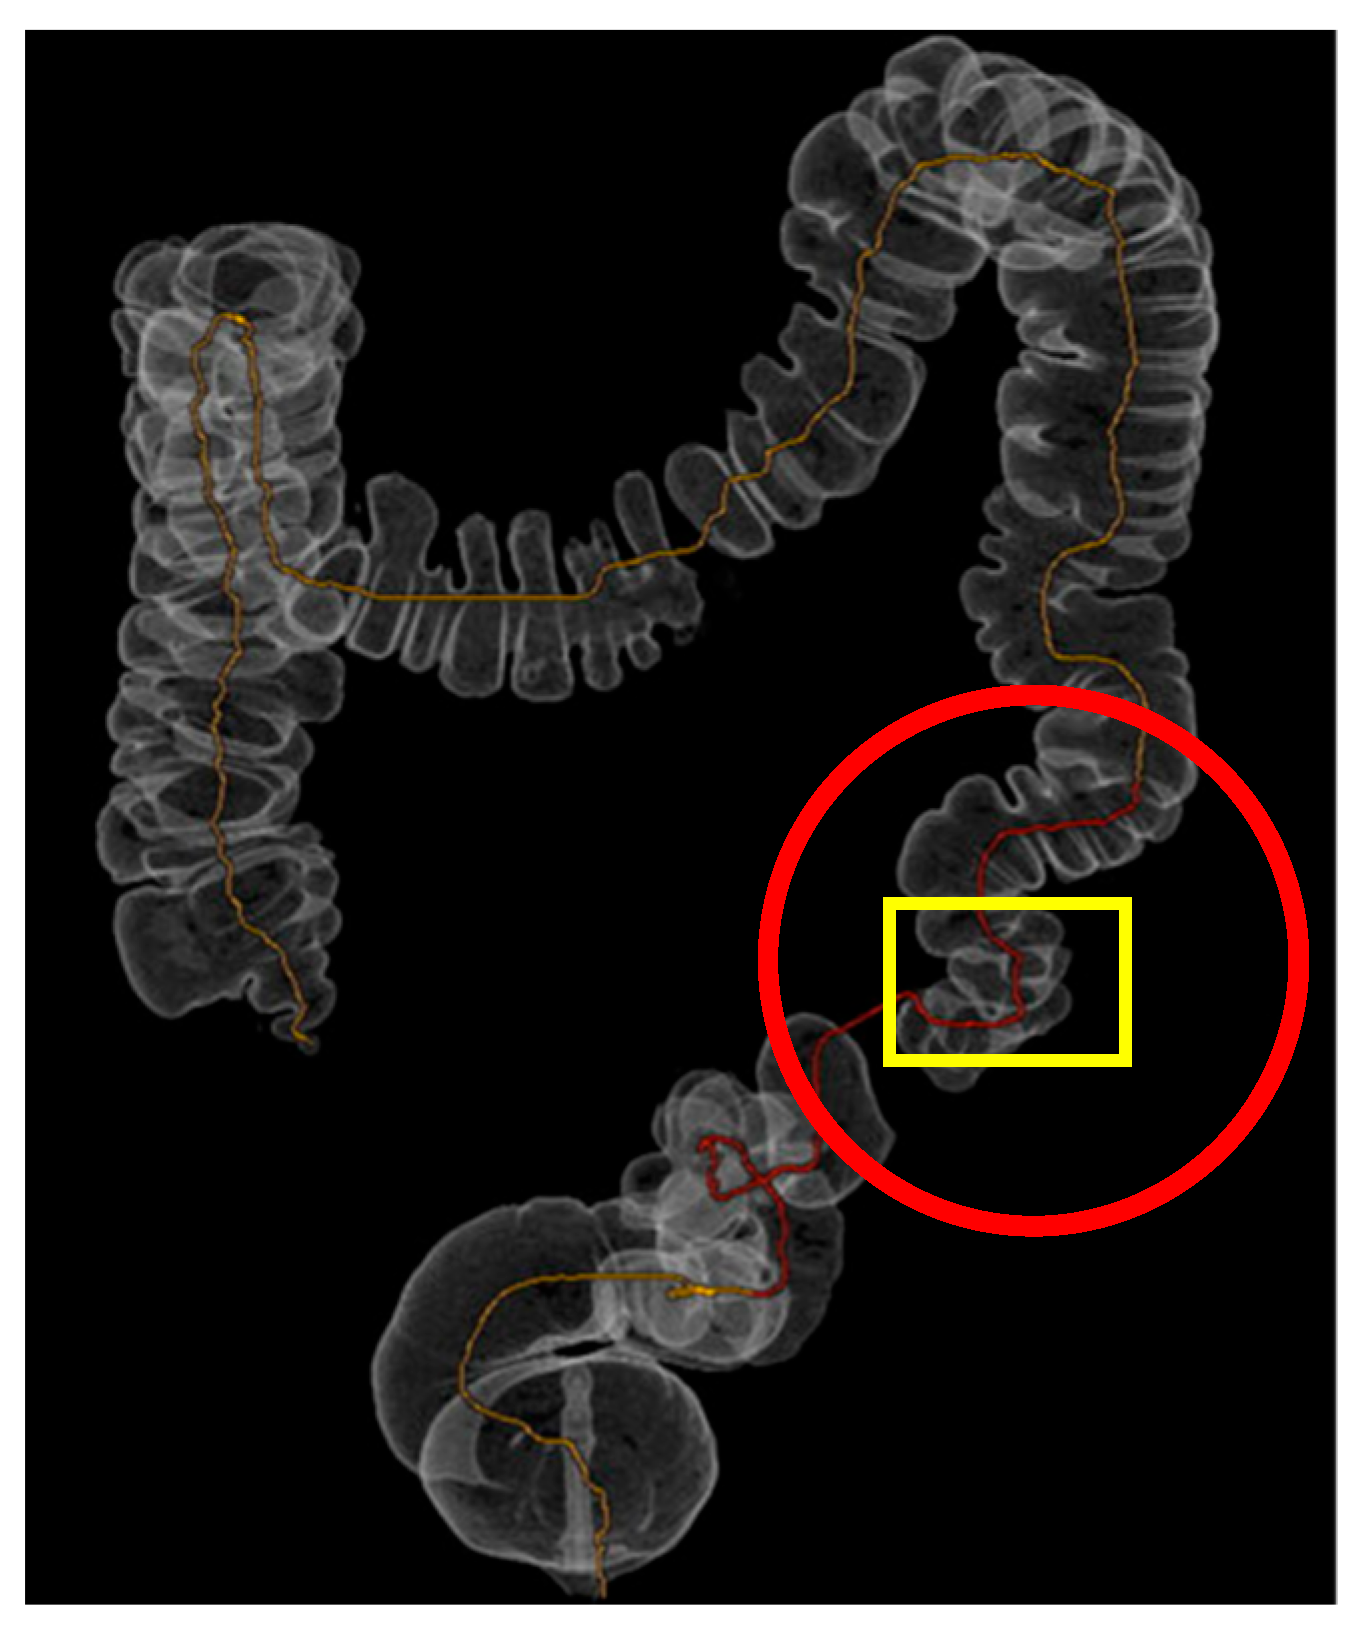

| Extent of diverticulosis | Massive diverticulosis of sigmoid and descending colon | Same finding confirmed with clearer visualization of segmental involvement |

| Stenotic area | Suspected narrowing, poorly defined | Stenotic segment clearly delineated, with precise localization and extension |

| Anatomical relationships | Limited perception of spatial relations | Improved understanding of relationship between diseased colon and surrounding structures |

| Surgical planning implications | Suggestive of need for resection | Supported decision for left hemicolectomy |

| Tactile/spatial perception | 2D visualization only | Physical 3D model provided tactile and spatial feedback useful for team discussion and planning |